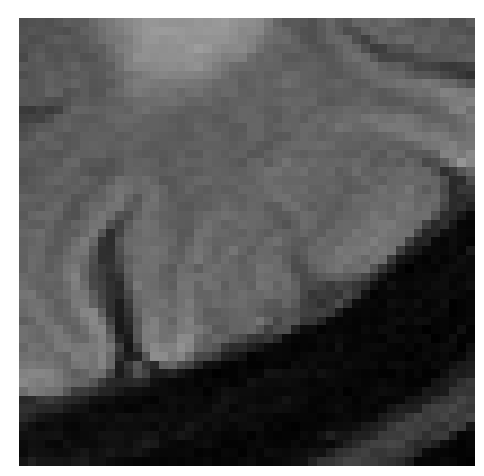

Figure 3: Examples of Reconstruction Results. Rows 1 and 3: The Ground truth (GT) fully sampled image, the reconstructed images obtained by the three models (1-3), NPB-REC, baseline, E2E-VarNet trained with Dropout, and the Std. map derived from our method for acceleration rates R=4𝑅4R=4, R=8𝑅8R=8, respectively. Rows 2 and 4: The corresponding annotated ROIS of the edema and resection cavity.

Fig. 3 presents examples of reconstruction results obtained by (1) our NPB-REC approach, (2) the baseline, and (3) Monte Carlo Dropout, for equispaced masks with two different acceleration rates R=4𝑅4R=4 and R=8𝑅8R=8. Table 1 presents the mean PSNR and SSIM metrics, calculated over the whole inference set, for the three models. our NPB-REC approach achieved significant improvements over the other methods in terms of PSNR and SSIM (Wilcoxon signed-rank test, pmuch-less-than\ll1e-4). The improvement in the reconstruction performance can be noted both quantitatively from the metrics especially for masks with acceleration rate R=8𝑅8R=8 and qualitatively via the images of annotations, where our results shows less smoothness than that obtained by Dropout.